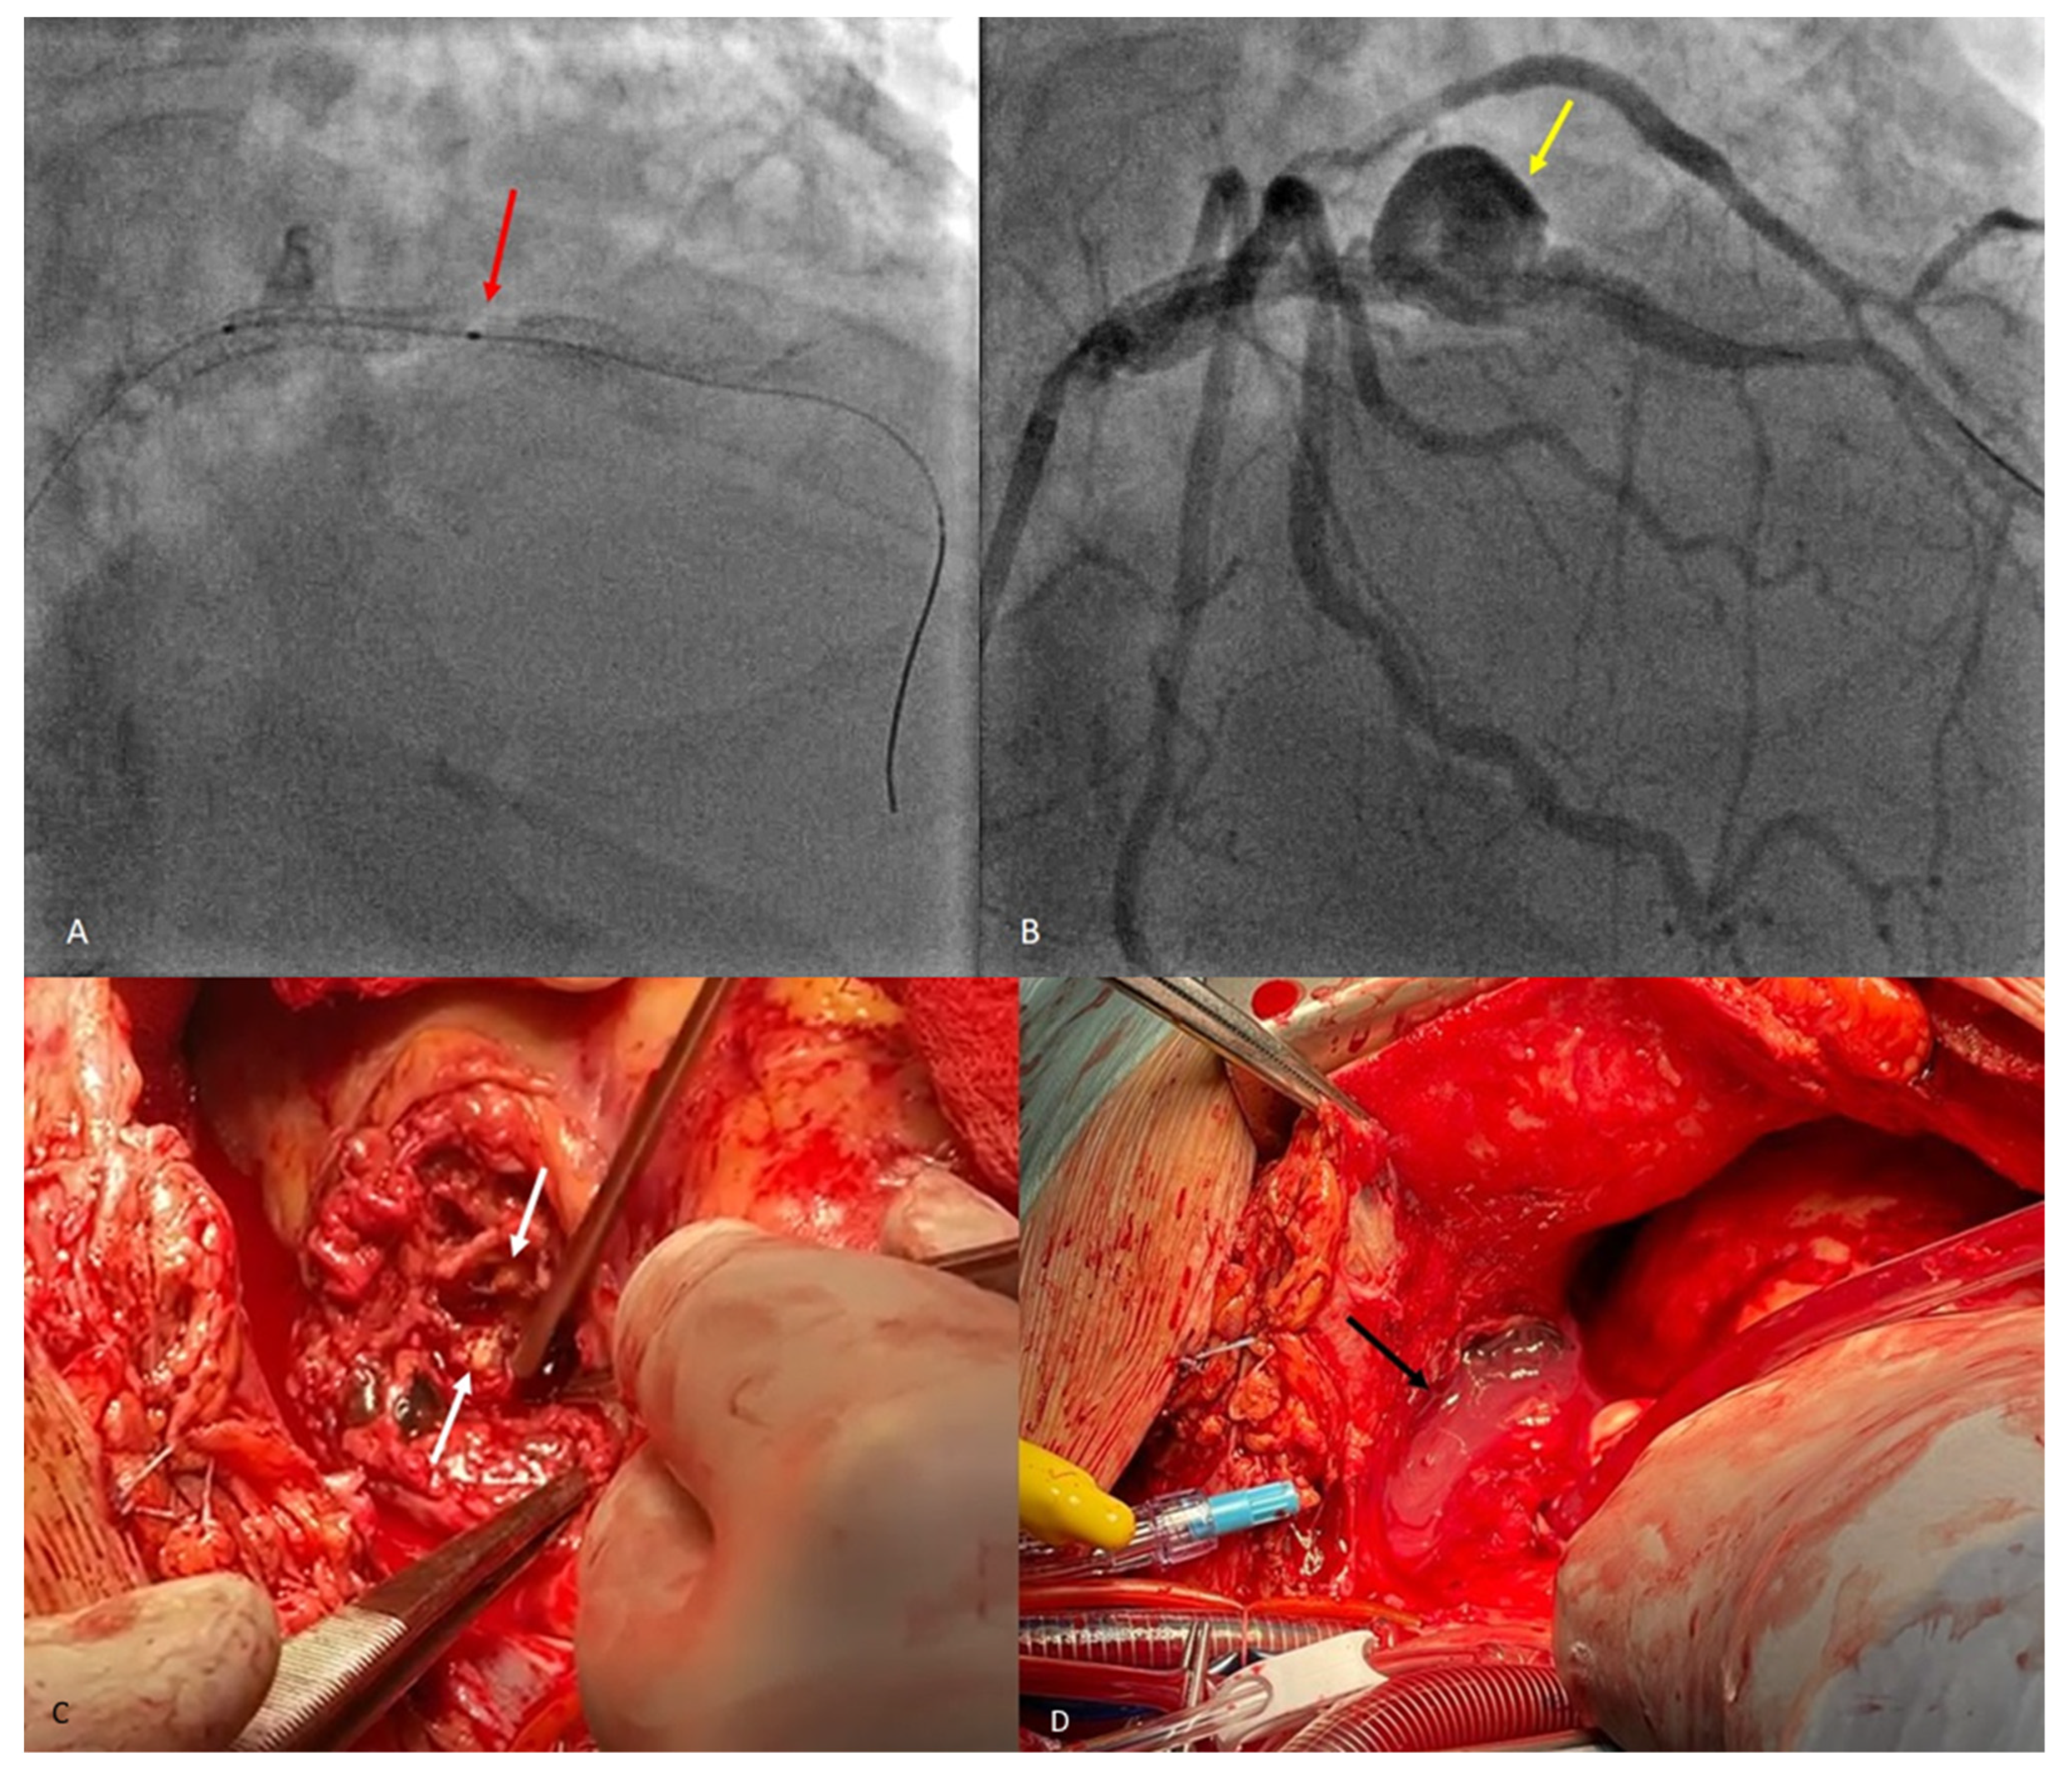

Figure 1. A 63-year-old male patient, with dyslipidemia, hypertension, diabetes mellitus type 2, history of smoking, severe coronary disease, and prior acute myocardial infarction was referred to the emergency department with constrictive chest pain and sweating for 6 h. The patient had a history of coronary stent implantation in the right and anterior descending coronary arteries 6 years prior, and, upon initial examination, had blood pressure (BP) in both arms of 120/60 mm Hg, heart rate (HR) of 90 bpm, regular rhythm, normal heart sounds on auscultation, no dyspnea or signs of systemic or pulmonary congestion. Blood tests revealed increased levels of markers of cardiac necrosis, mild anemia, hyperglycemia, hyperuricemia, hyponatremia, and acidosis. ECG showed ST-segment elevations of up to 5 mm in leads V2–V6, Q waves in leads V1–V4, and bifascicular block with complete right bundle branch block and left anterior fascicular block. TTE reveals dyskinesia of the affected myocardial territory, namely the interventricular septum and the anterolateral wall in the apical two-thirds, respectively, systolic dysfunction, with an ejection fraction of 30%. Coronary angiography revealed severe ostial stenosis of the LAD ((A), red arrow) and intrastent thrombotic occlusion in the first two segments of the LAD ((B), orange arrow), which is why pharmacologically active stents XIENCE PRO 4.0/23 mm, BIOMIME 2.5/13 mm, and BIOMIME 4.0/13 mm were implanted in the proximal and mid parts of the LAD, each stent extending beyond the previous one, with the restoration of blood flow ((C,D), green arrows).